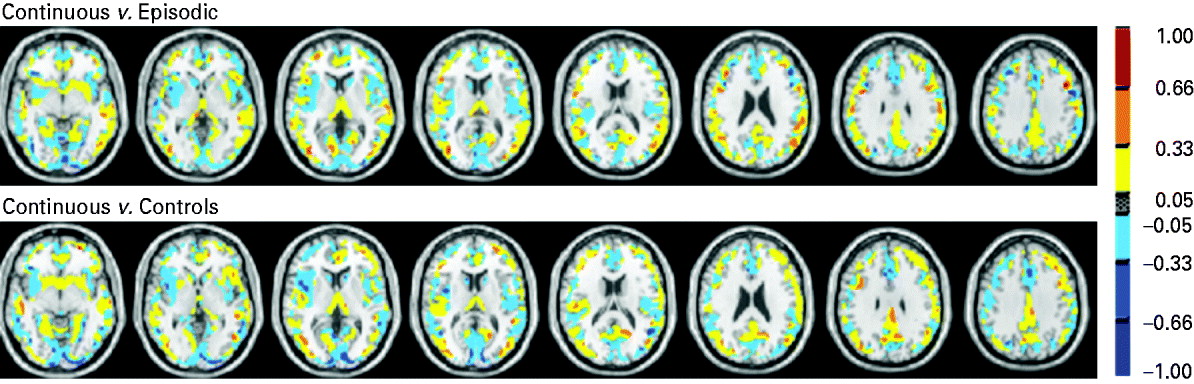

The anatomical regions with the highest contribution to the discrimination of the continuous group from the episodic and the healthy control groups included the cingulate and parahippocampal gyri, basal ganglia and thalami (Fig. 2, Tables 3 and 4).

Fig. 2. Discrimination map or support vector machine (SVM) weight vector: continuous versus episodic course (top), continuous course versus healthy individuals (bottom). The colours represent the weight of each voxel in the classification function (the red scale represents positive weights and the blue scale represents negative weights). The SVM weight vector is a linear combination or weighted average of the support vectors, that is the training examples that are most difficult to separate and define the decision boundary. The weight vector is therefore a spatial representation of the decision boundary. Every voxel contributes with a certain weight to the decision boundary or classification function. Given a positive and a negative class (e.g. +1=episodic group; −1=continuous group), a positive weight for a voxel means the weighted average in that voxel was higher for the episodic group, and a negative weight means the weighted average was higher for the continuous group. Because the classifier is multivariate by nature, the combination of all voxels as a whole is identified as a global spatial pattern by which the groups differ (the discriminating pattern). Therefore, the discrimination map should not be interpreted as a standard statistical parametric map resulting from a mass-univariate statistical test to find group differences, and no local inferences should be made based on the SVM weights.

Although, with these methods, it is not possible to make local inferences on the discriminating regions, it is noteworthy that the anatomical regions with the highest contribution to the discrimination between groups include the cingulate and parahippocampal gyri, the basal ganglia and the thalami, which have been consistently reported as important in the pathophysiology of schizophrenia (Ellison-Wright et al. Reference Ellison-Wright, Glahn, Laird, Thelen and Bullmore2008).